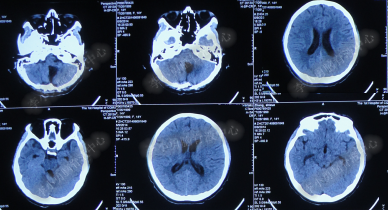

患者因恶心、呕吐伴头痛头晕,自行服药后无法自行缓解,于2014年5月29日就诊位于重庆的著名的三甲肿瘤医院,查全脑CTA和CT后诊断为“小脑蚓部占位伴幕上脑积水”(图-1、图-2)。

图-1:2014年5月29日全脑CTA

图-2:2014年5月29日头部CT